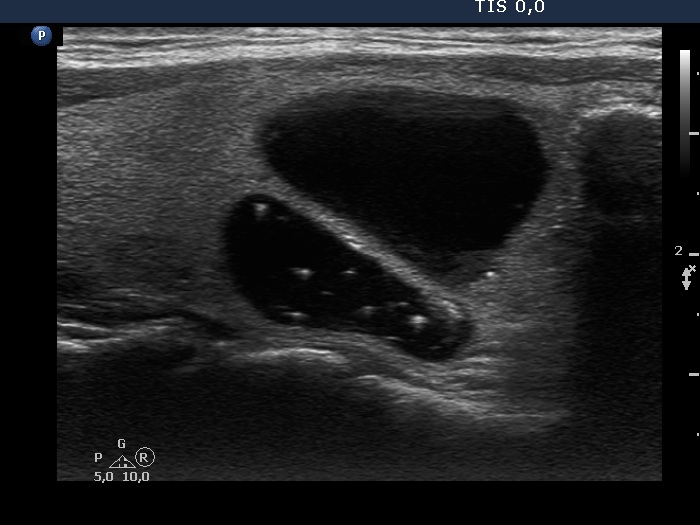

Study on 100 consecutive patients with thyroid nodule - case 030 (ultrasonographic picture 3)

Right lobe, another longitudinal view. Typical comet-tail artifacts can be seen. Note the bright granule in the lower part (right in the image). This is located dorsal to a tiny cystic area, therefore it should not be regarded as a microcalcification.